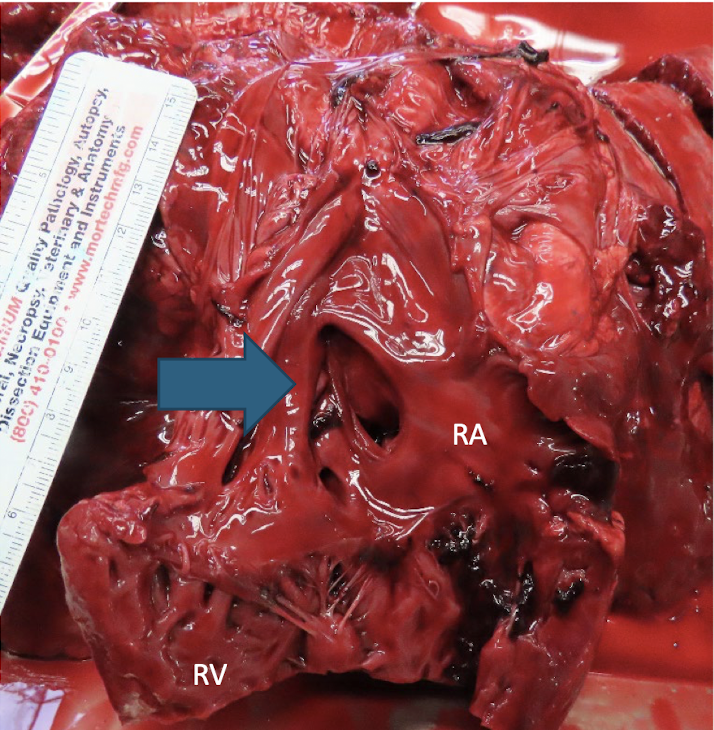

<p>What is this showing?</p>

What is this showing?

ventricular septal defect